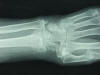

Carpo normal